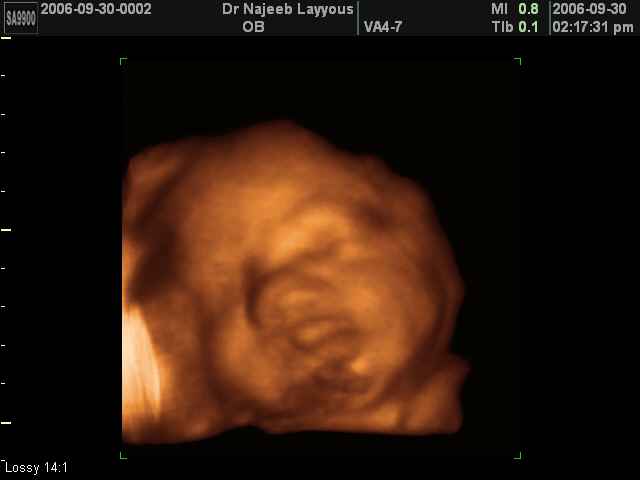

- صور لوجه الجنين في داخل الرحم

- صور جانبية لرأس الجنين

- صور لتصرفات الجنين داخل الرحم

صور لتصرفات الجنين داخل الرحم بجهاز الالتراساوند ثلاثي الأبعاد | الدكتور نجيب ليوس